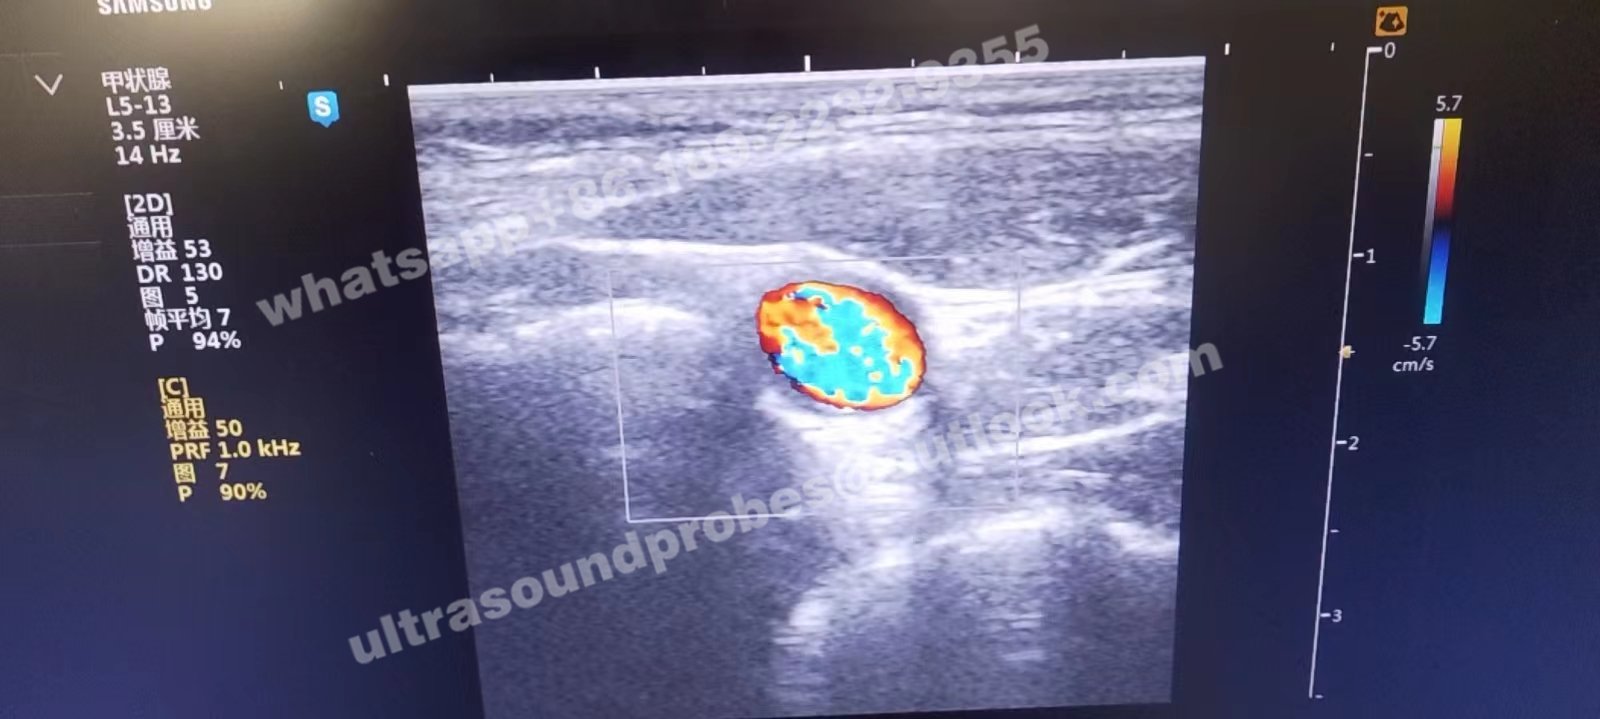

Samsung Medison L5-13is Original Ultrasound Probe for V10

Samsung Medison L5-13is Original Ultrasound Probe for H60

- Condition: original used,good working

- Warranty: 30 days

- Compatibility: Samsung Medison H60